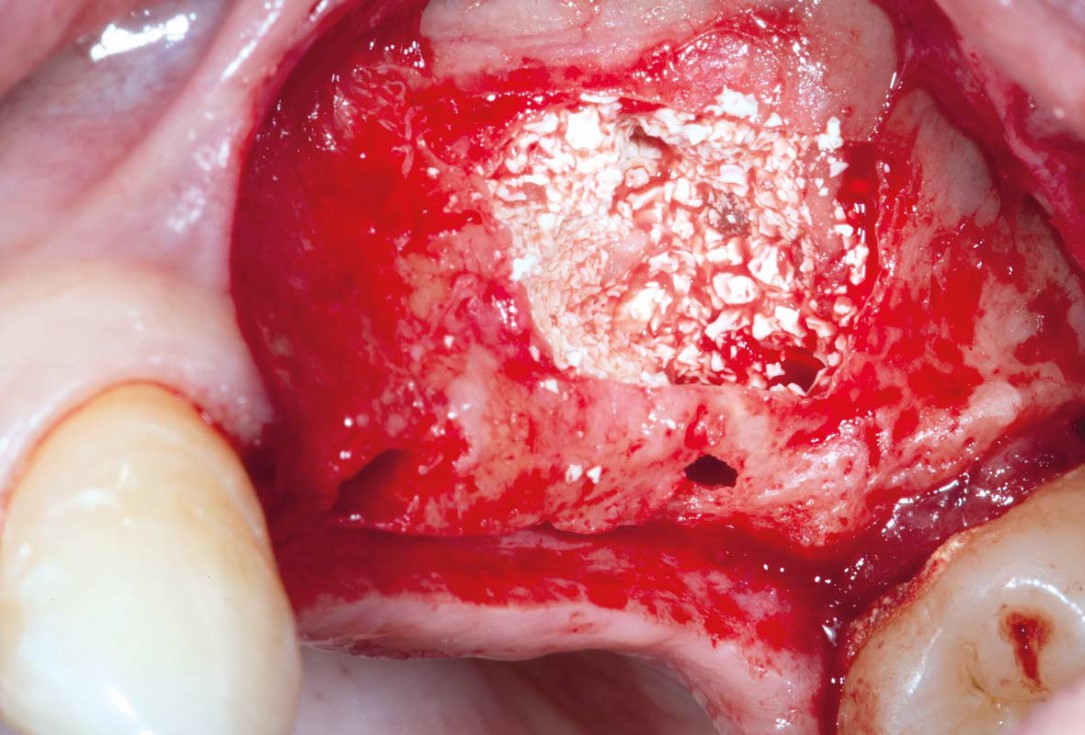

Sinus Floor Elevation with maxgraft® bonering - Dr. B. Giesenhagen

X-ray scan reveals initial situation with maxillary bone height in regio 15 of 1.5 mm